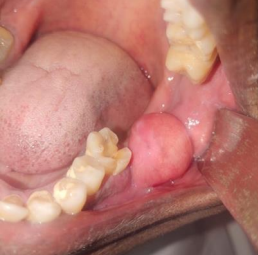

The swelling was pedunculated measuring 3x3cmm in size seen in vestibule in relation to 37,38. It is soft, fluctuant and non-tender on palpation. The mucosa over the lesion appears normal and blood investigation appears to be in normal limits.

Figure 1